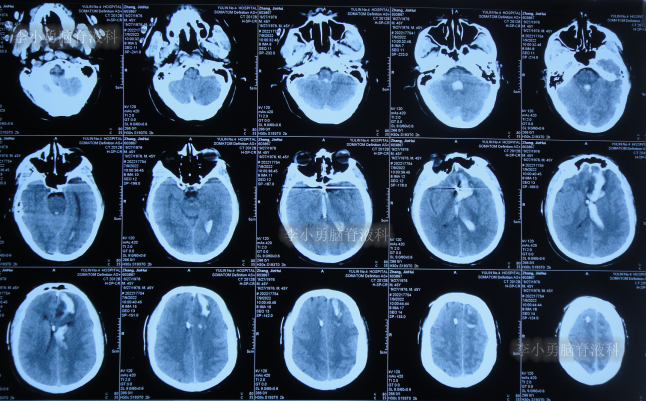

患者于2022年7月8日凌晨突发头痛,伴有胡言乱语,右下肢明显乏力,被家属送至附近的陕西省榆林市某医院,查头颅CT示脑出血(图-1),考虑脑动脉瘤破裂;当即给予了DSA检查发现前交通动脉瘤(图-2)。

图-1:2022年7月8日头颅CT

脑动脉瘤栓塞术后4天即2022年7月12日,查头颅CT示仍有积血(图-4)。

图-4:2022年7月12日头颅CT

拔除引流管后10天即2022年7月25日(脑动脉瘤栓塞术后17天),查头颅CT示脑室周水肿,仍有少量积血(图-5);仍间断发热,且脑脊液白细胞仍高,脑脊液浑浊。

图-5:2022年7月25日头颅CT

因病情未见好转,患者在该院治疗25天即2022年8月2日(脑动脉瘤栓塞术后25天),转到家乡的河北省某三甲医院继续治疗,查头颅CT示脑动脉瘤栓塞术后状态(图-6),仍间断高热,给予每日行腰椎穿刺治疗。

图-6:2022年8月2日头颅CT

该院治疗20余天时间内,虽每天进行腰穿治疗,但期间3次查头颅CT均显示脑室持续的扩张(图-7、图-8、图-9)。

图-7:2022年8月9日头颅CT

图-8:2022年8月14日头颅CT

图-9:2022年8月15日头颅CT